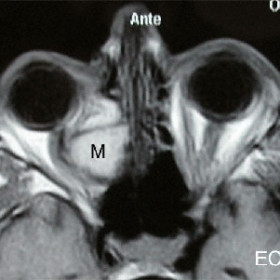

Ethmoidal mucocele (M) displacing the optic nerve

Magnetic resonance imaging (MRI) demonstrates an ethmoidal mucocele (M) displacing the optic nerve.